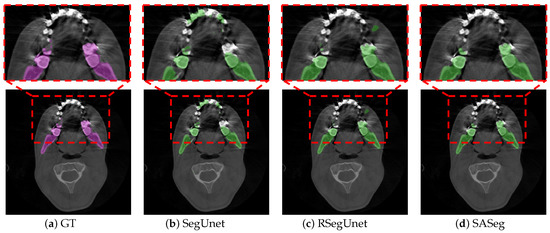

3. Results

3.1. Method Comparison